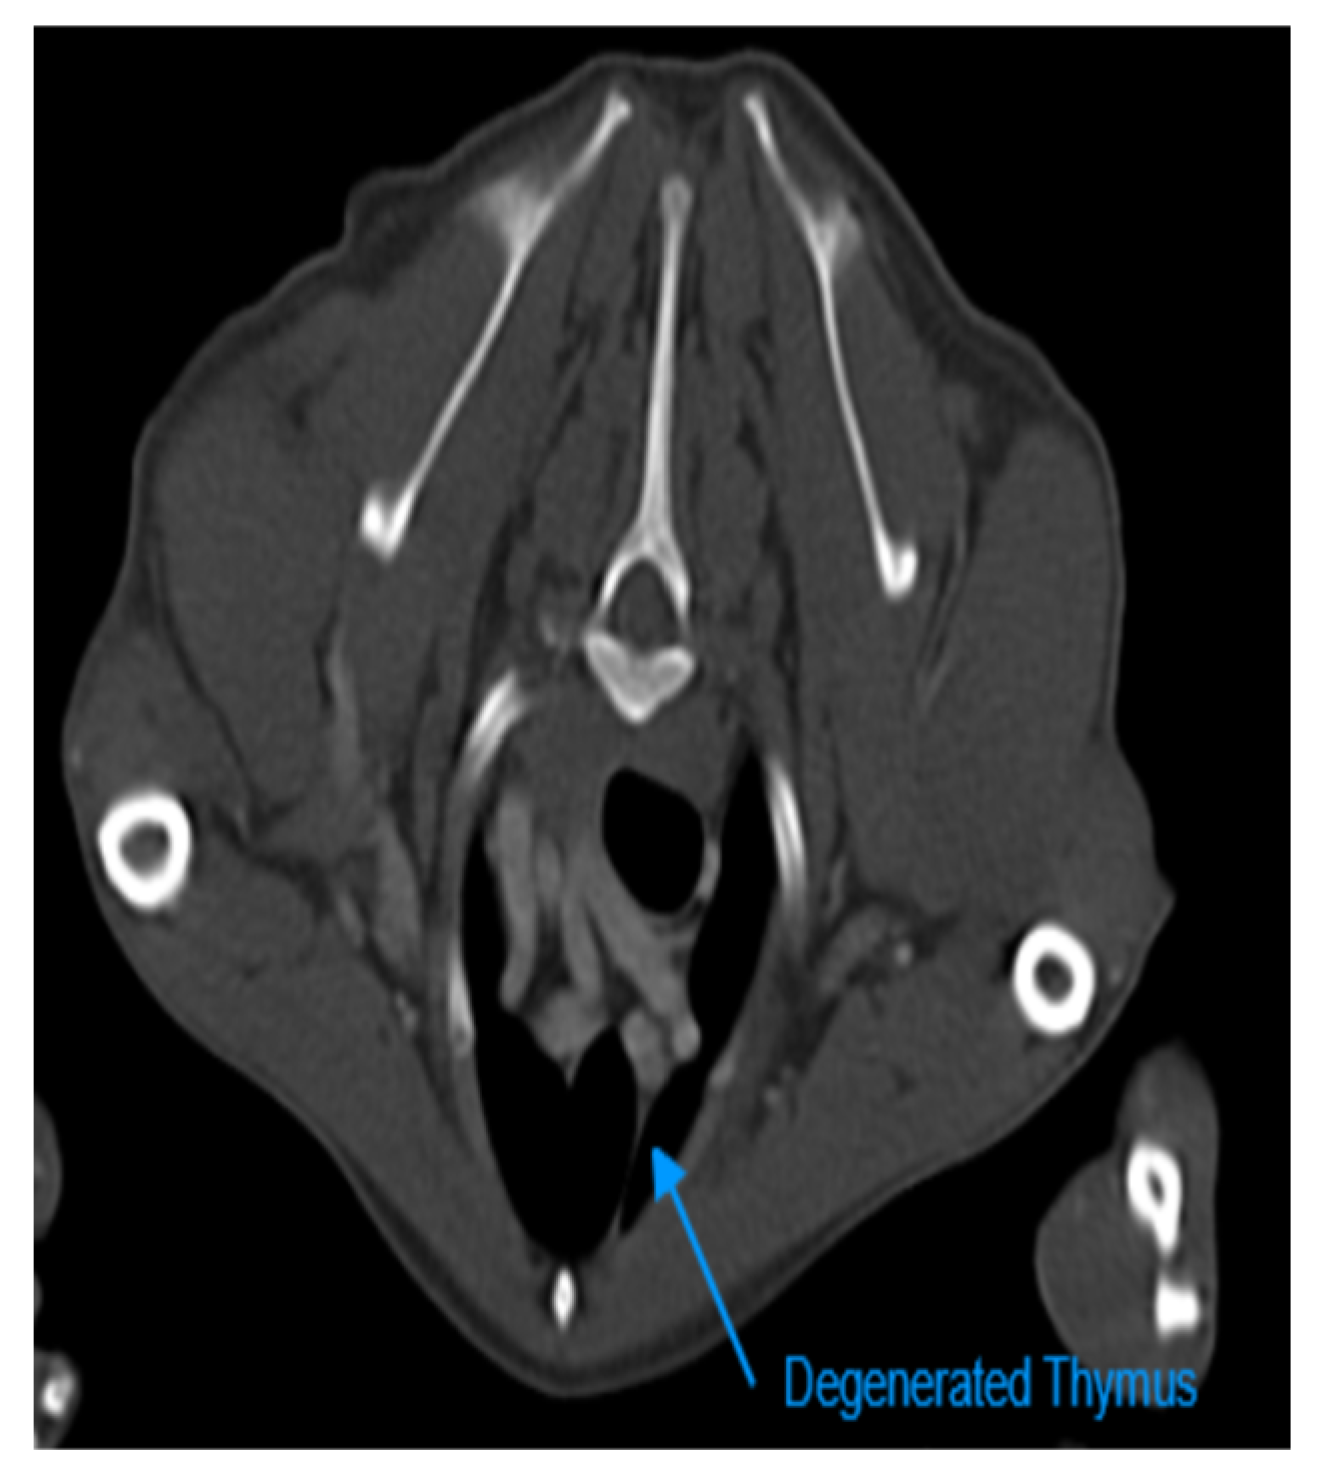

In the present study, the thymus gland was visible in 104 of 150 cases, but the distinct lobes of the thymus were not distinguishable. The visible thymus glands were noted with soft tissue component and homogenous appearance, a combination of soft tissue and fat component based on the degree of involution with heterogenous (mottled) appearance and only fat component (Figure 1 and Figure 6). We accounted the thymus glands with complete fat degeneration for non-visible thymus glands (Figure 6). The anatomical and topographical location of the thymus is shown in Figure 7. The thymus' dorsal border begins at the ventral aspect of the vessels in the cranial mediastinum and ends at the dorsal aspect of the sternebra. In dorsal and sagittal views, it was extended caudally up to the pericardial region and merged with the pericardium on the left side. The visibility percentage in group 1 was 100%. The minimum and maximum ages in group 1 were three and six months, respectively. In groups 2 and 3, the thymus was visible in 86.7% of cases and it was not notable in 13.3% of cases. The minimum and maximum ages with visible thymus in group 2 were seven and 12 months, respectively. This group includes three 12-month-olds and one 11-month-old case with a non-visible thymus. In group 3, the youngest and oldest cases with a visible thymus were 1.5 and 2 years old. The patients with a non-visible thymus were two years old. In group 4 the visibility percentage was 53.3% and the thymus was not visible in 46.7% of patients. The youngest and oldest patients with visible thymus in group 4 were three and six years old. The visibility percentage of group 5 was 20% and the maximum age with visible thymus was nine years old (Table 4 and Table 6).

Figure 7. Illustration of Anatomical and Topographical Location of Thymus in Transverse Section of Post-contrast CT Scan Examinations. The Left Image is at the Level of T2 and Belongs to a 3-month-old Male Mixed-breed Dog. The Thymus Highlighted with Yellow Colour is Visible with Complete Soft Tissue Component in this Patient. The Right Image is also at the Level of T2 and Belongs to a 4-year-old Female Dog. In this patient, the Thymus is Completely Degenerated and Highlighted with Yellow Colour. T: Trachea, E: Esophagus, LSCa: Left Subclavian Artery, BCT: Brachiocephalic Trunck, LITa: Left Internal Thoracic artery, S: Sternebra, RITv: Right Internal Thoracic Vein, RITa: Right Internal Thoracic Artery, CrVC: Cranial Vena Cava, TV: Thoracic Vertebra.